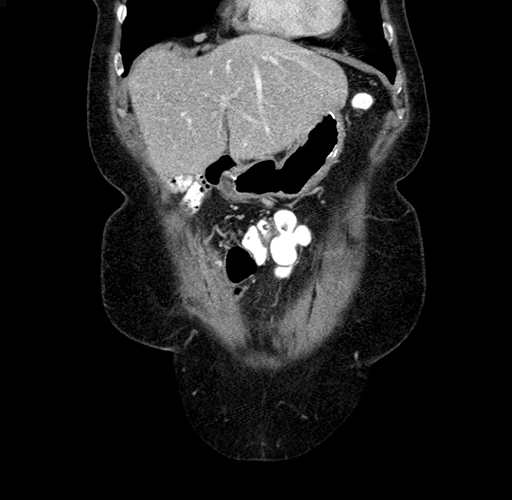

Coronal Venous